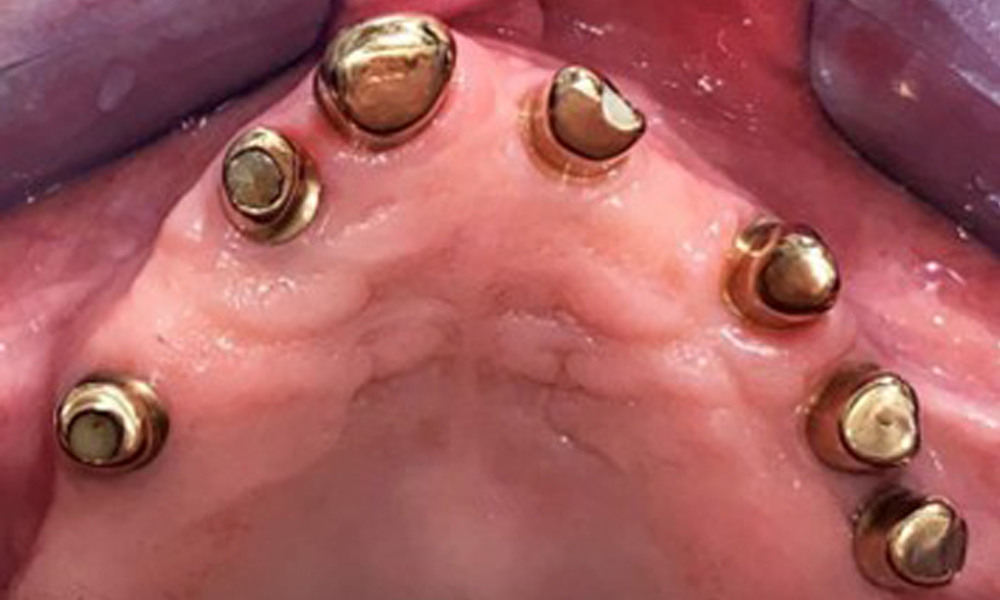

Оклузален изглед: Горна челюст със зъб и телескопични протези, поддържани от импланти

Фиг. 2: Оклузален изглед: Горна челюст със зъб и телескопични протези, поддържани от импланти